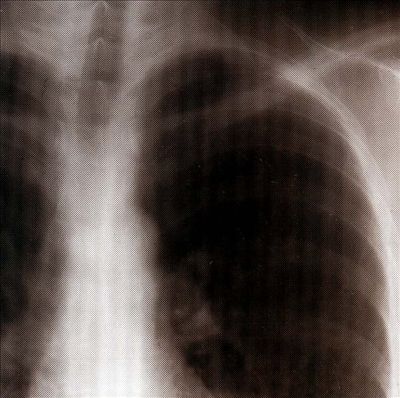

Für seine zweite Veröffentlichung für Touch (nach »Send«) ist John Duncan einmal mehr in die (Un-)Tiefen der menschlichen Psyche eingedrungen und positioniert die Koordinaten von »the beauty of sound« und »human evil« in einem bisher unerforschten Gebiet. Ähnlich wie z. B. auf »The Crackling« (zusammen mit Max Springer, Trente Oiseaux, 1996) geht Duncan der Frage nach, was der »sound of energy« sein könnte. Innerhalb des 46-Minuten-Stücks lassen sich mehrere Einheiten erkennen, die erst im Gesamtzusammenhang in einander fließen, weil die Sub-Parts durch schlichte Cuts getrennt sind. Diese Teile verweisen auf die unterschiedlichen innerkorporalen Regionen, von denen der modifizierte Herzschlag, der tap internal, der beruhigendste und gleichzeitig unterschwelligste ist. Vor zu lautem Hören sei gewarnt: Rhythmus-Angleichungen zwischen Herz- und Hertzfrequenz könnten nicht nur zufällig sein. Wieder mal heavy listening in high quality.